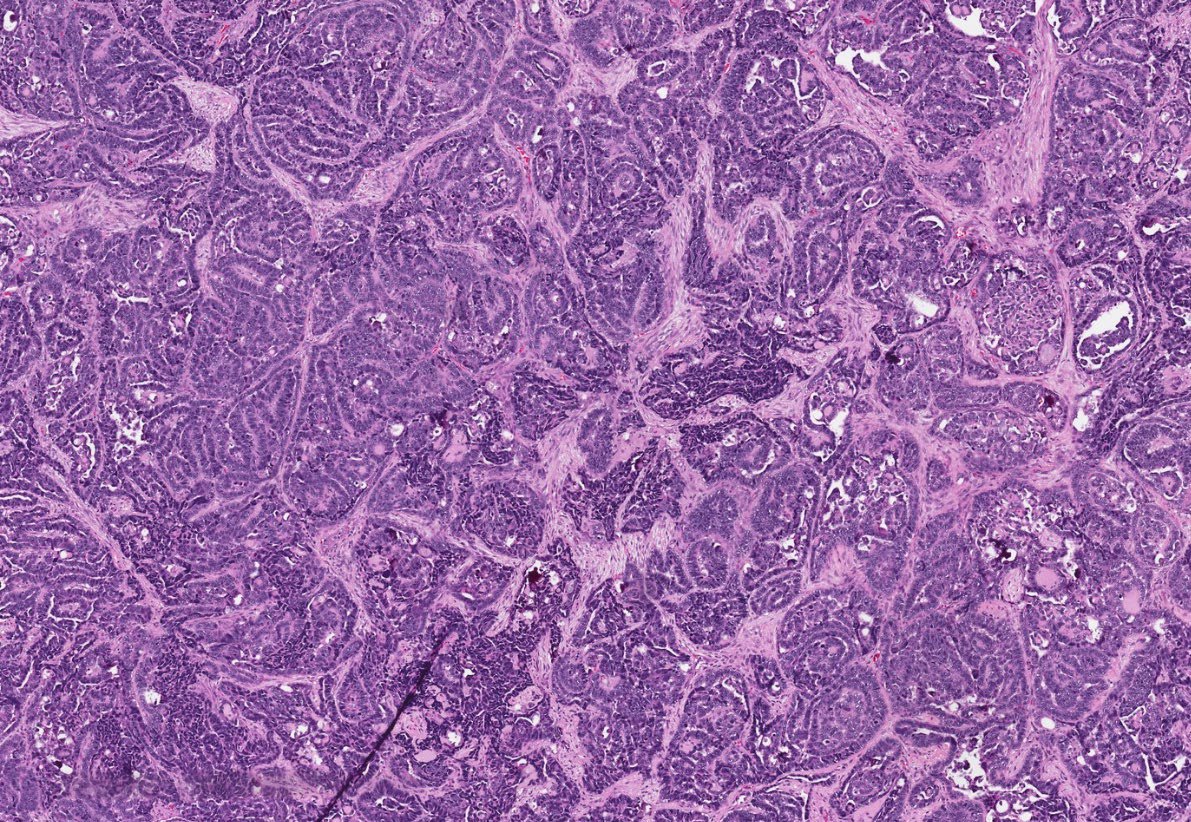

30 F. Mass in lumen of femoral vein. Diagnosis?

WSI digital slides: kikoxp.com/posts/21727

Immunostains: kikoxp.com/posts/21729